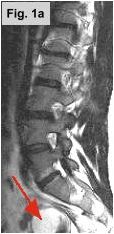

Fig. 1a-c: MRI of the L-spine (sagittal T2 weighted, coronal scout, and coronal MR Myelogram, respectively) demonstrates an incidental 4-5 cm cystic-appearing mass in the right pelvis on limited views of the pelvis. Fig. 2: a helical CT image of the pelvis, revealing a 4x5 cm low-density mass in the right hemipelvis to the right of the uterus. Fig. 3: Pelvic ultrasound shows a moderately enlarged right adnexa measuring 5 cm with low-level echoes.

IMAGING FINDINGS:  Fig. 1a-c show MRI images of the L-spine (sagittal T2 weighted, coronal scout, and coronal MR Myelogram, respectively).  They demonstrate mild scattered disc bulges and an incidental 4-5 cm cystic-appearing mass in the right pelvis on limited views of the pelvis. Incidentally, the MR Myelogram (Fig. 1c) also nicely shows the thecal sac and renal collecting systems.  Fig. 2 shows a helical CT image of the pelvis, revealing a 4x5 cm low-density mass in the right hemipelvis to the right of the uterus with CT density of about 20 Hounsfield units on pre- and post-contrast images.  A repeat transabdominal and endovaginal pelvic ultrasound with Doppler performed at AIC (Fig. 3) showed a moderately enlarged right adnexa measuring 5 cm with low-level echoes.